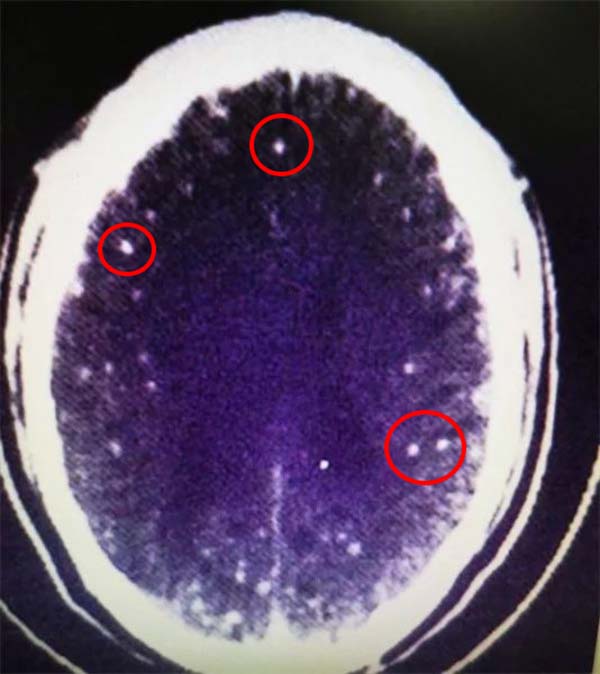

Kết quả chụp MRI cho thấy người đàn ông này bị nhiễm ký sinh trùng nghiêm trọng trong não.

Các bác sĩ tin rằng nguyên nhân có thể là do những lát thịt chưa được nấu chín có chứa sán dây mà người đàn ông này đã ăn. Ký sinh trùng đã xâm nhập vào não thông qua hệ tiêu hóa.

Bác sĩ giải thích thêm rằng, trứng của ký sinh trùng có thể đã nở trong đường tiêu hóa, sau đó được vận chuyển đến nhiều bộ phận khác của cơ thể, trong đó có cả não.